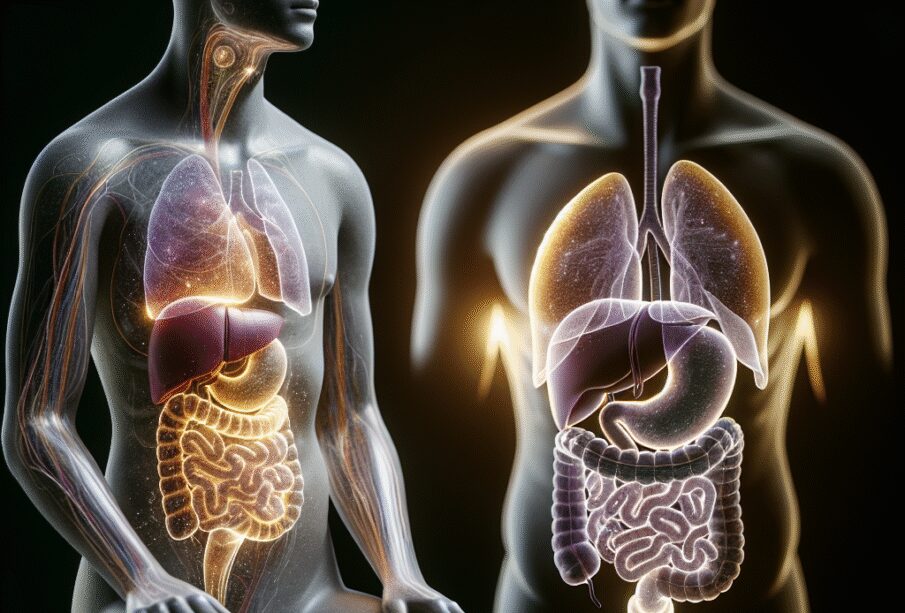

Το τέντωμα στην περιοχή των πλευρών θεωρείται σύμπτωμα και όχι αυτόνοση πάθηση, και μπορεί να εμφανιστεί σε διάφορες περιστάσεις. Στα συγκεκριμένα σημεία βρίσκονται σημαντικά όργανα όπως το ήπαρ, ο σπλήνας, το στομάχι, το έντερο, το πάγκρεας και το διάφραγμα. Επομένως, η αίσθηση μπορεί να προέρχεται όχι μόνο από τους μύες, αλλά και από εσωτερικά όργανα ή ακόμη και το νευρικό σύστημα.

- Το ήπαρ τοποθετείται στη δεξιά πλευρά, ακριβώς κάτω από το πλευρικό τόξο.

- Ο σπλήνας βρίσκεται στην αριστερή πλευρά, επίσης κάτω από τα πλευρά.

- Το στομάχι και το πάγκρεας εντοπίζονται περισσότερο κεντρικά και αριστερά.

- Μέρος του εντέρου εκτείνεται τόσο δεξιά όσο και αριστερά.

- Το διάφραγμα, ένας λεπτός μυϊκός υμένας, χωρίζει τη θωρακική κοιλότητα από την περιοχή της κοιλιάς.